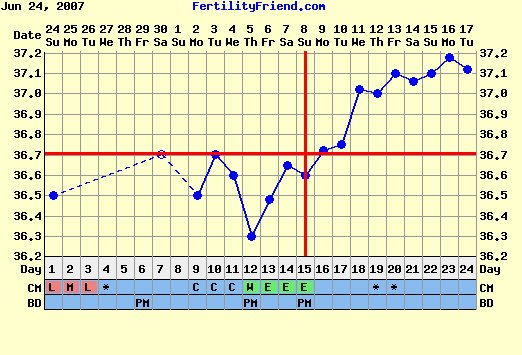

Egyáltalán milyen ciklusom lesz, hiszen clostil előtt, 32-38 volt az átlag, de becsúszot egy -két 50 napos is.